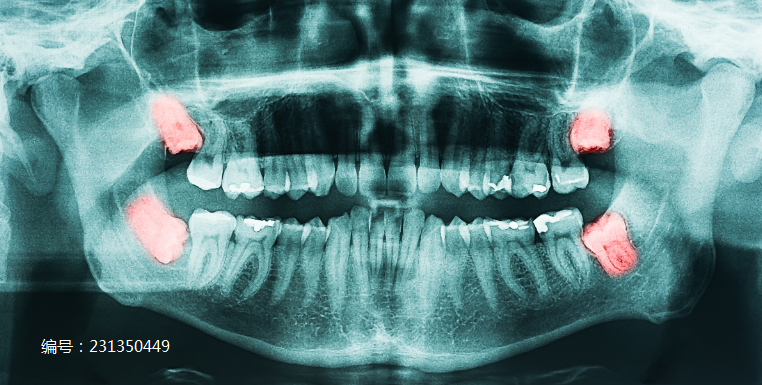

通常埋在牙槽骨里,不易被察觉,只能通过拍X光片诊断出。